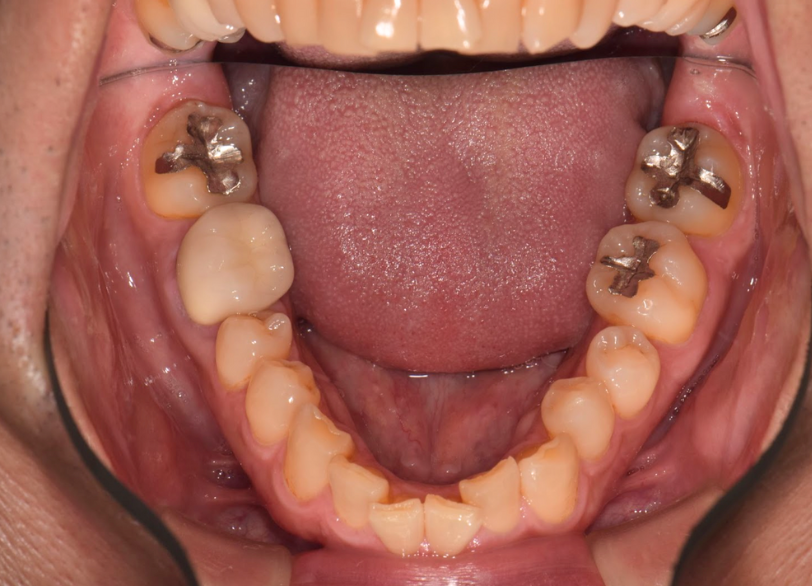

術前 右上7の銀歯

術後 右上7の銀歯がセラミックに置き換わっている(1.5時間で銀歯の除去からセラミック装着まで完了)

歯と歯の間にもう蝕があり2本同時に1日で銀歯除去からセレック置き換え治療を行った